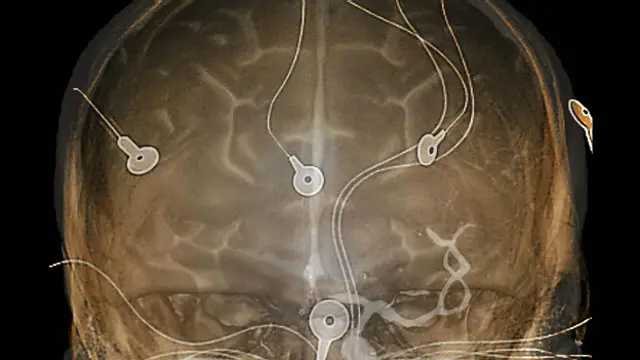

Лишь в 1920 гг. им стала доступна электроэнцефалография (ЭЭГ) - технология считывания электрических сигналов мозговой активности.

Поначалу ЭЭГ применяли в довольно необычных целях - например, чтобы посмотреть, насколько подходят друг другу обрученные, или для изучения мозга преступника.

Однако эту технику стали использовать и с целью исследования мозговой активности пациентов с некоторыми заболеваниями (например, с эпилепсией), чтобы понять, что происходит с мозгом во время припадков.

Автор фото, SPL

Самые первые электроэнцефалографы предполагали довольно инвазивную с точки зрения пациента процедуру. Во время экскурсии по обширным запасникам Музея науки Дэйбин показала мне один из таких древних аппаратов.

Электроэнцефалографы прошлого использовались как для считывания мозговых сигналов, так и для стимулирования мозговой активности.

Но только лишь при помощи электрических сигналов ученые все равно не могли получить полную картину мозговой деятельности. Требовалось что-то новое.